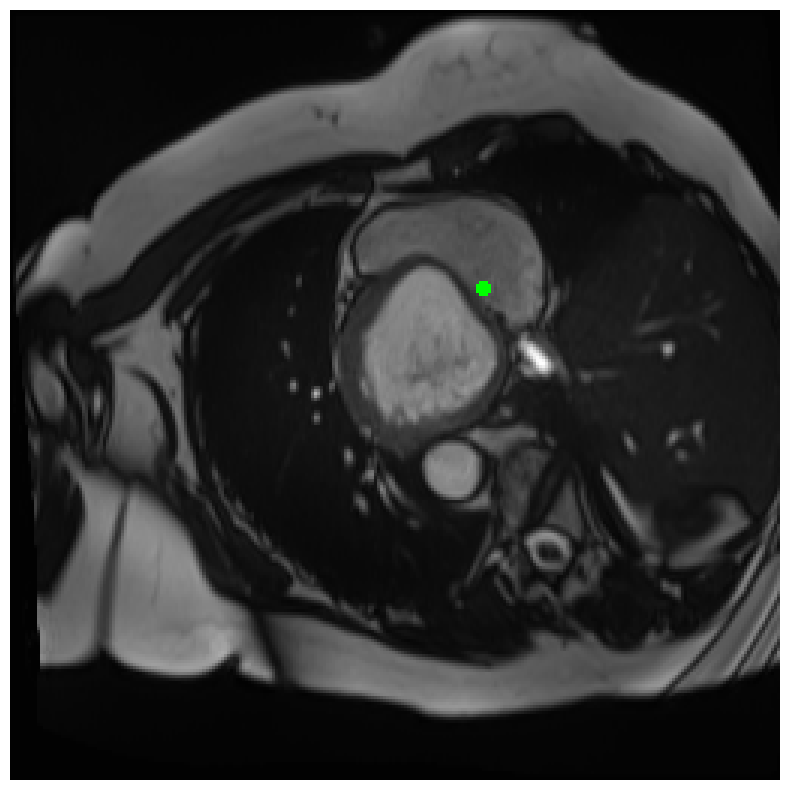

Generally, given an exact, full annotation of an object, such a Euclidean signed distance map encodes also information on the shape of an object. But when using a weak ground truth , where and , inferring a correct extent and shape of the objects is nontrivial. As shown in 1(b), Euclidean distance calculated from a point label source grows radially, regardless of the actual shape of the object, and thus makes little sense from an information point of view. Under the assumption of intra-object homogeneity and inter-object contrast (w.r.t intensities), this problem can be circumvented to a degree by using a distance function that takes also intensity values into account. An example of a commonly used distance measure with an intensity component is the Geodesic distance ([34]). Let denote a path between , with and being neighbors under a chosen adjacency relation. Reusing the notation from before, a Geodesic distance map from the boundary of the ground truth class , , can be defined as

Both the Intensity and the Minimum barrier distance are defined exclusively on the image intensity space. However, from the examples of distance map in 1(d), we can notice that the values still increase somewhat radially from the annotation. This behaviour is similar to the one of the Geodesic distance in 1(c) (which actually includes the spatial proximity in its definition), and is due to the summing operator in the general Geodesic distance definition in Equation 3. While the intensities of two neighboring pixels on a path may be the same, that will rarely be the case in real life, noise riddled images. This makes the Intensity distance function approximately monotonically increasing with increasing length of the path (in space), even on paths where the intensity is mildly fluctuating (e.g. consider a path with even pixels intensity value of and odd pixels intensity value of ). One could thus argue that such a definition of a distance, despite being based exclusively on intensities, is still capable of loosely encoding the spatial distance information.

On the other hand, while we can see that the MBD based maps are similar to Geodesic and Intensity ones (1(e)) with respect to the object shape recovery, they have a less pronounced and smooth increase in the values outward from the source point.

In contrast to Euclidean distance, the Geodesic, Intensity and Minimum barrier distance maps all encode contrast sensitivity and preserve the object structures by harnessing the intensity information of the underlying image. This holds even when calculated from point sources. In practice, using such maps for network training could mean a lower penalty for false positives that occur farther from the point annotation but are close to it in intensity. Thus still enabling the propagation of a sort of shape information (as it can be inferred from the raw image intensities).